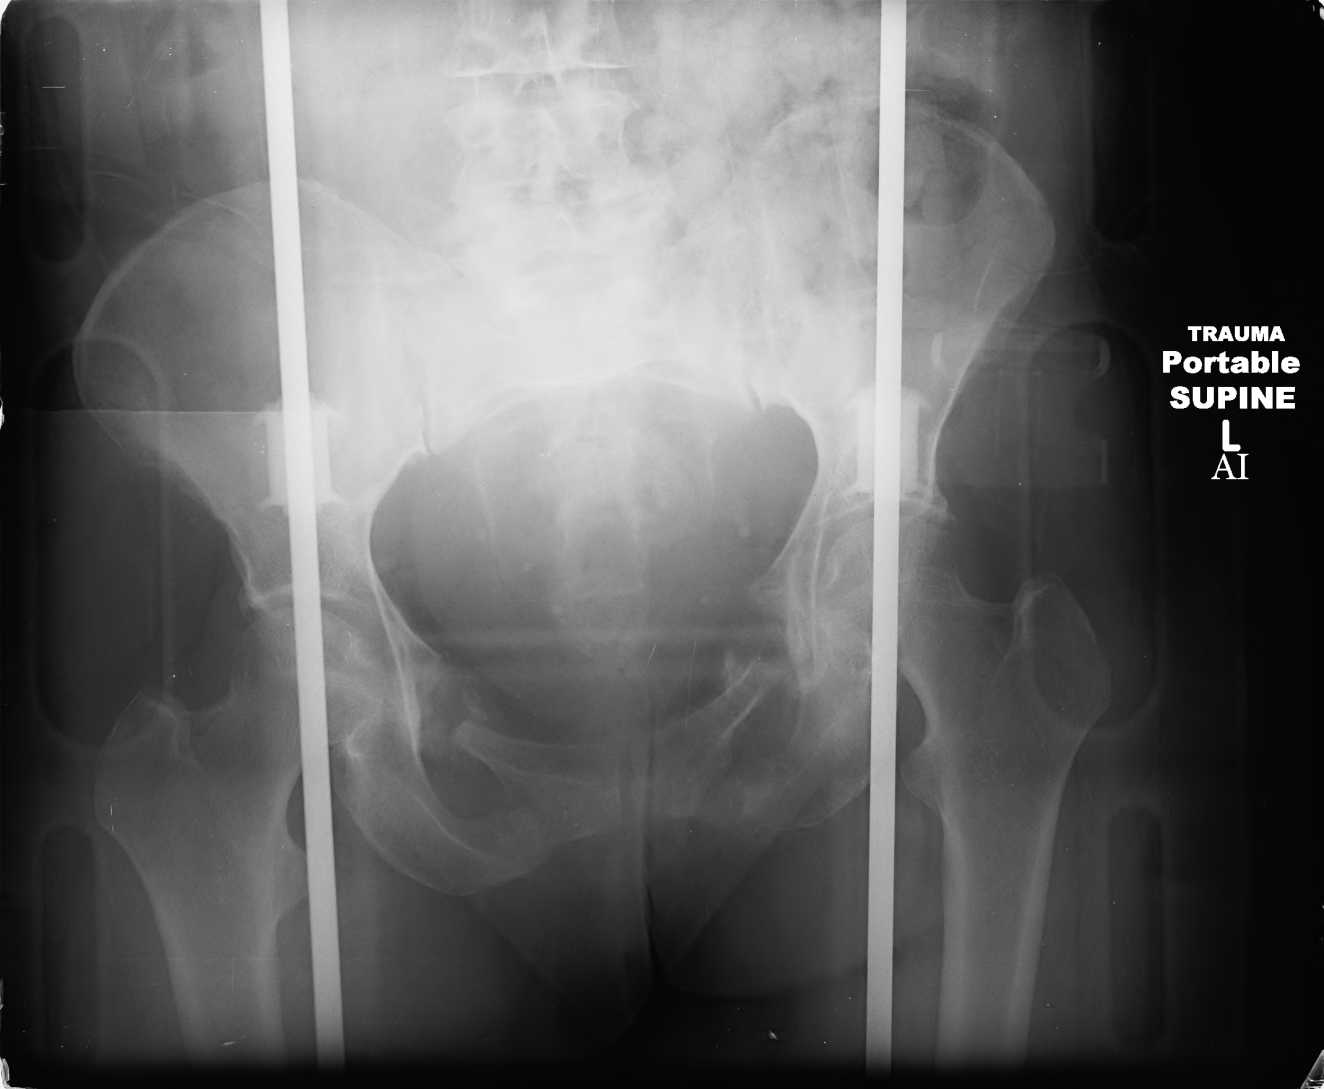

Here are a recent patient’s example slides...

Percutaneous Fixation

(B) Ramus-Retrograde

2 TransIliac-TransSacral

Upper Segment